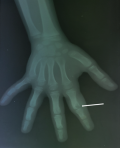

Diagnostic assessment: laboratory investigation revealed a normal complete blood count, with slightly elevated C-reactive protein (CRP) levels at 15 mg/L (normal value < 6 mg/L), and an elevated erythrocyte sedimentation rate (ESR) of 20 mm/h (normal value < 10 mm/h). An anteroposterior and lateral radiographs of the hand showed an oblique osteolytic lesion of the cortex and the medullary space in the head and neck of the proximal phalanx of the index finger (Figure 1). An MRI of the hand showed a corticomedullary lesion in the metaphyseal-epiphyseal region of the first phalanx of the index finger, with a punctate osseous focus and significant perilesional edema, consistent with osteoid osteoma (Figure 2).

Figure 1: anteroposterior plain radiograph of the hand demonstrating an eccentric lytic lesion of the head and the neck of the proximal phalanx of the index finger (white arrow)